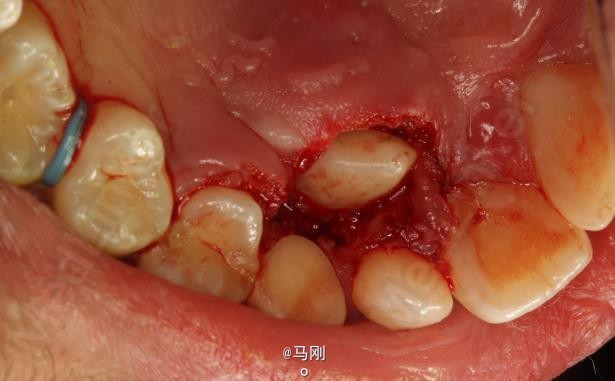

诊断 处理

处理:建议拔除右侧乳尖牙,并外科开窗牵引导萌13。患者同意治疗方案。签知情同意书。